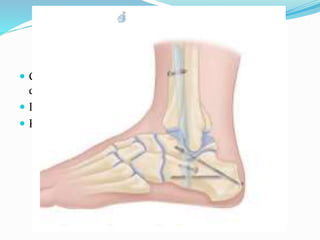

 Insert large, partially threaded, cannulated screws

(typically 6.5 to 8.0 mm) over guidewires .

 Three screws are ideal, but sometimes only two are

possible. The most desirable position is the so-called

“home run”. Screws positions are :

 1st screw : from the posterolateral tibia into the talar

neck/body

 2nd screw : proximomedial screw directed into the

posterior body of the talus

 3rd screw : proximal anterolateral to distal medial

screw or a distal lateral screw from the lateral process

of the talus directed proximal, posterior, and medial.